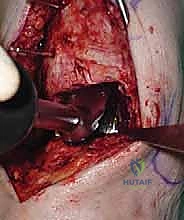

6. القطع العظمي الكاحلي (Talar Bone Cut)

بشكل مشابه، يتم توجيه دليل القطع نحو عظمة الكاحل (Talus) وإزالة السطح الغضروفي التالف وت